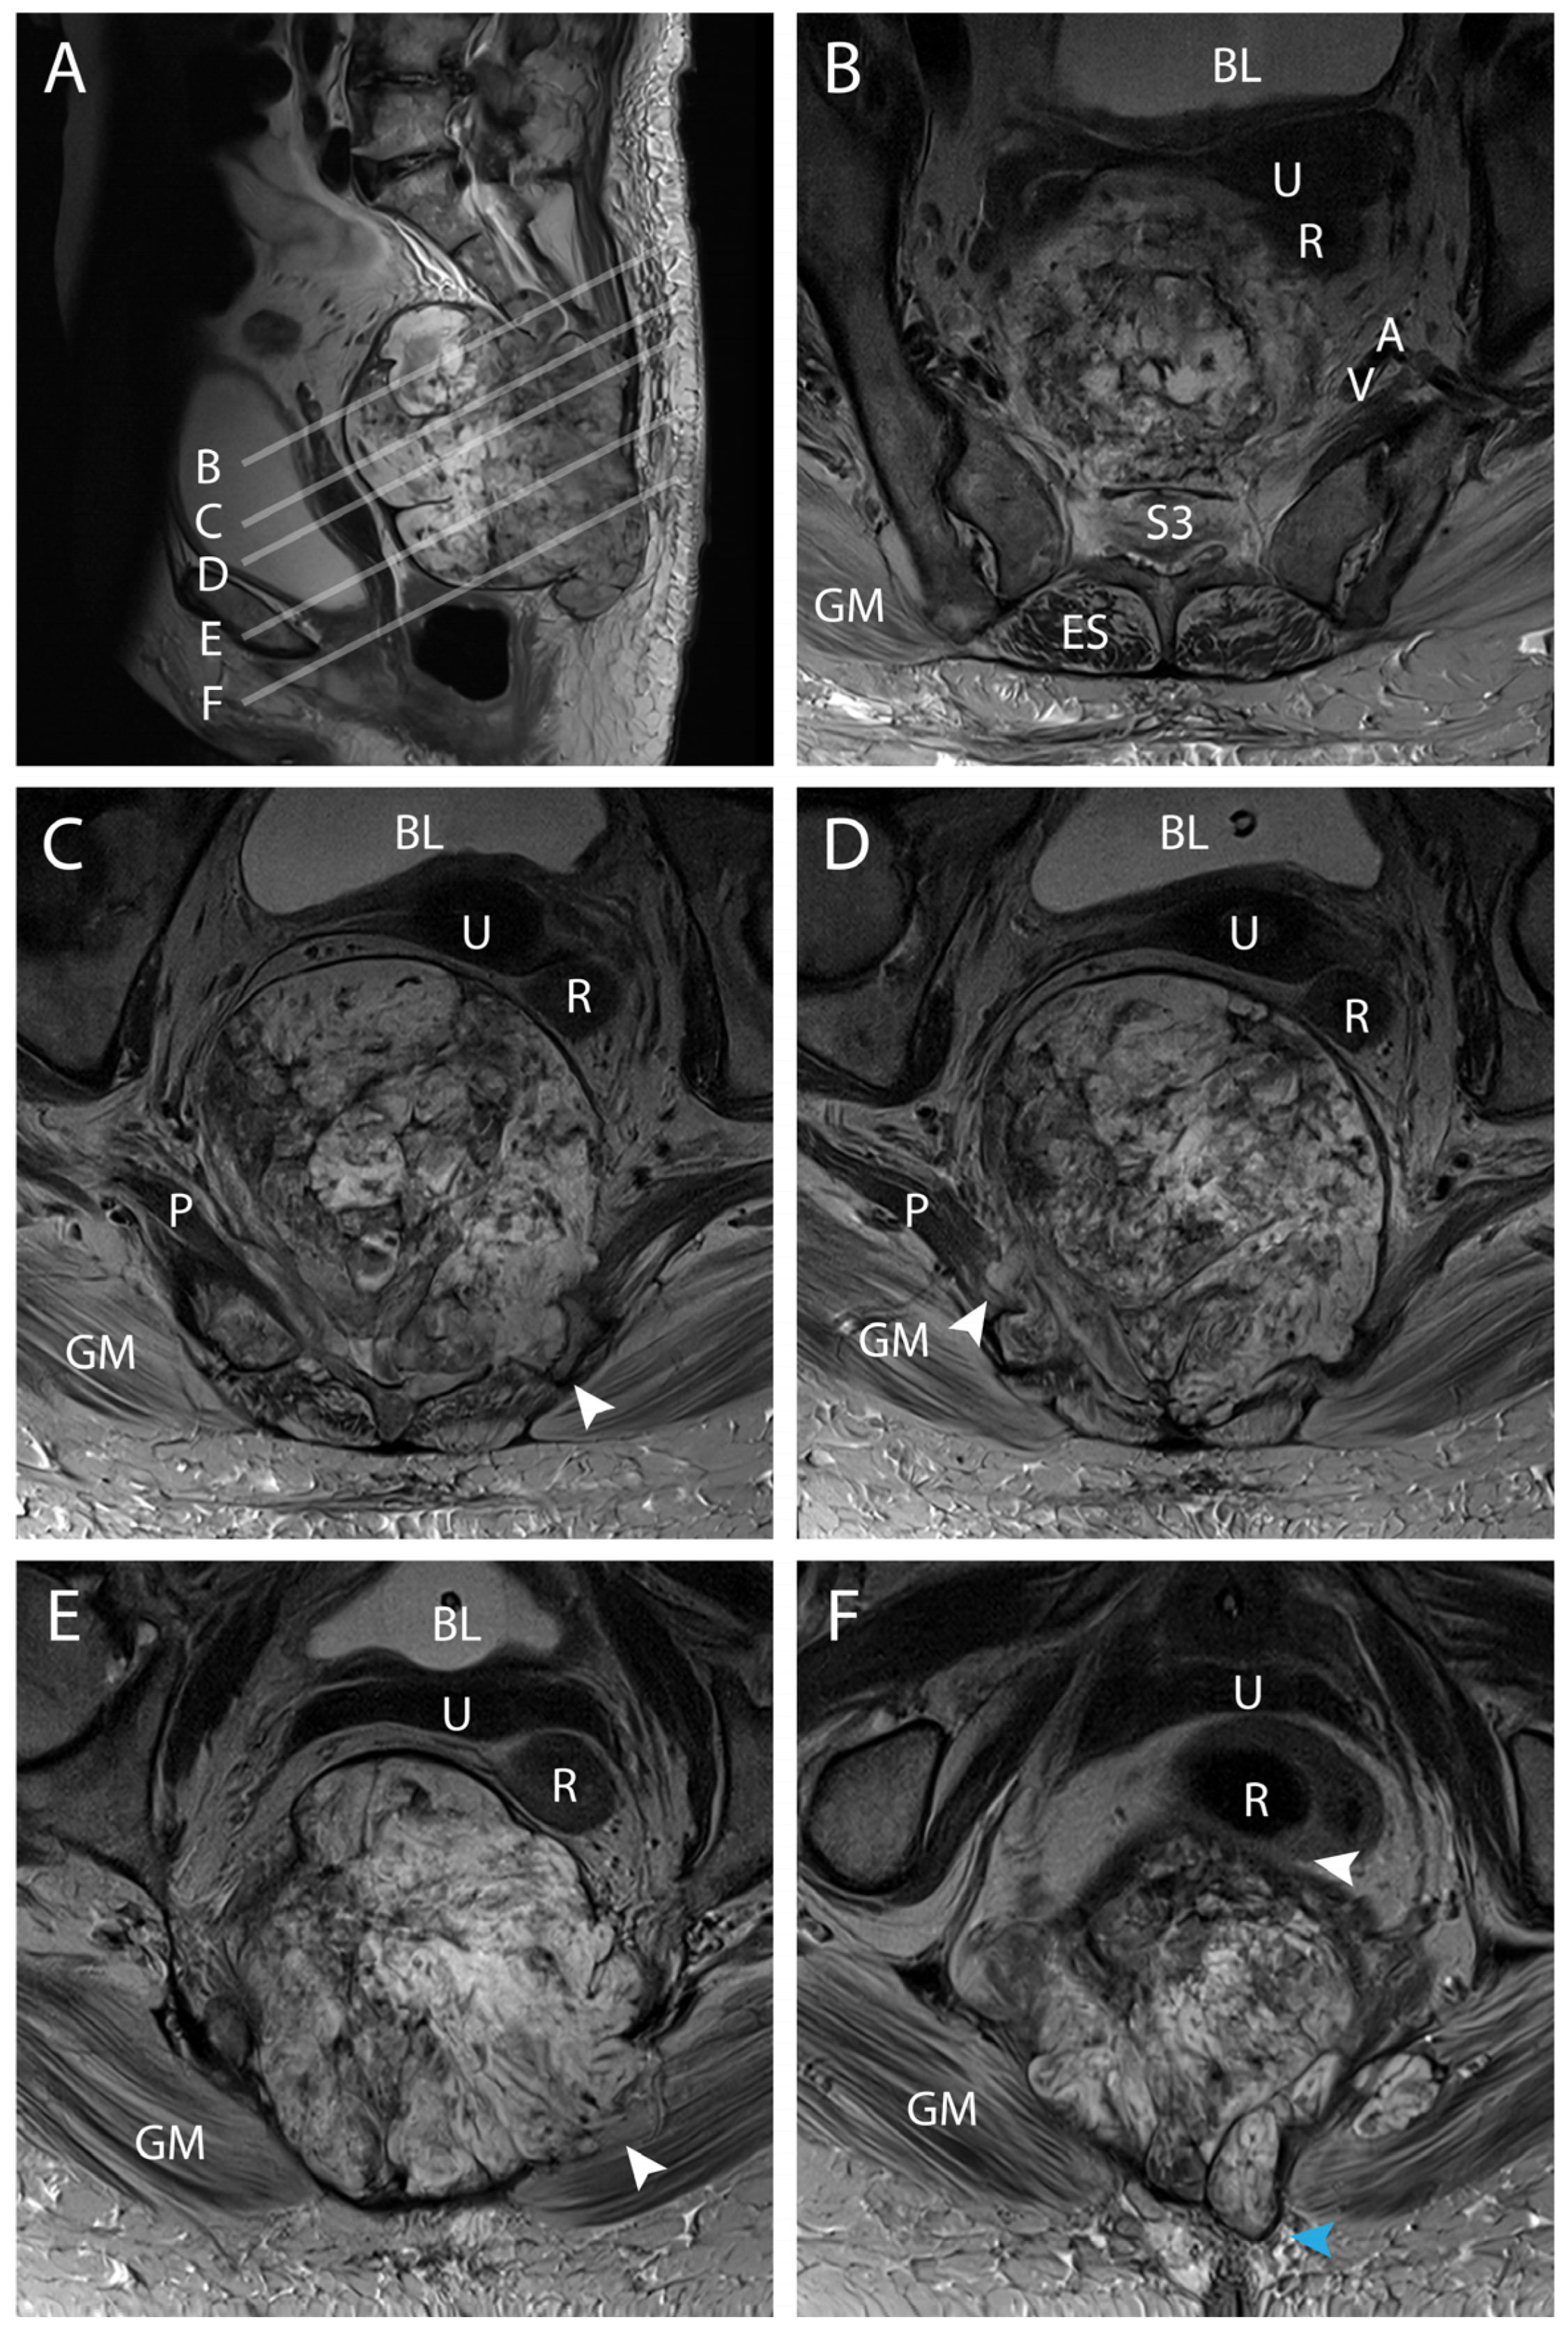

4. Results: Illustrative Case

4.1. Clinical Elements

4.2. Preoperative Planning